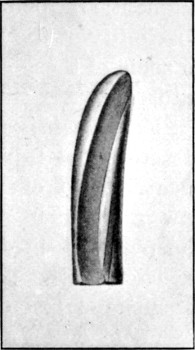

27. Normal Mauser Bullet83

34. Normal Lee-Metford Bullet89